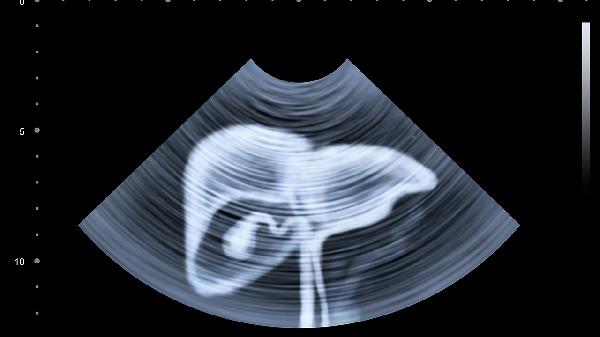

输尿管下段或膀胱结石可放射至左下腹,疼痛常突然发作呈绞痛性质,可能伴随血尿、尿频。结石形成与代谢异常、尿路梗阻有关,确诊需进行泌尿系超声检查。5毫米以下结石可尝试排石治疗,遵医嘱服用盐酸坦索罗辛缓释胶囊扩张输尿管,配合枸橼酸氢钾钠颗粒碱化尿液。每日饮水量需保持在2000毫升以上。